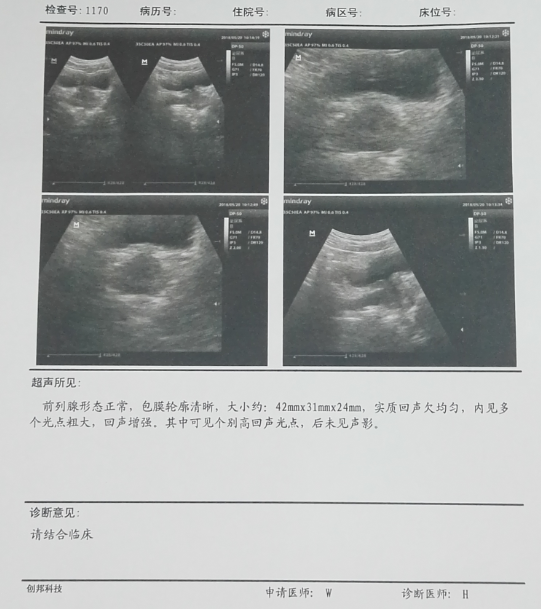

这位患者的前列腺b超可见他的前列腺形态正常,包膜轮廓清晰,大小约42*